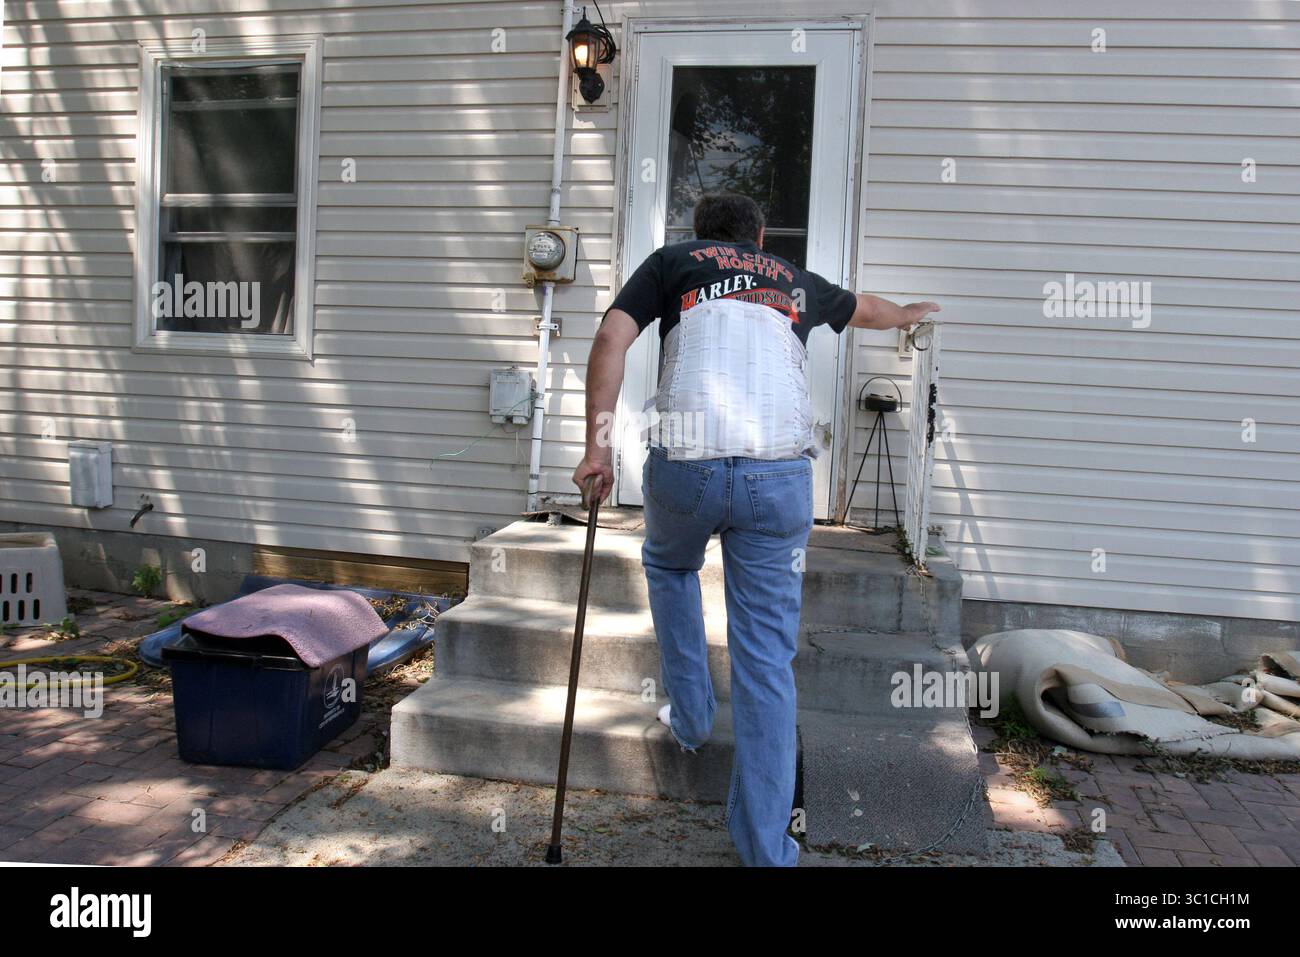

21 juin 2007 - Minneapolis, MN, USA - Don Gunnon a fait son chemin dans sa maison avec l'utilisation d'une canne pour marcher à cause des problèmes de dos causés par une balle logée près de la colonne vertébrale est par son nerf sciatique. Après la voiture de Gunnon a été volé il a été envoyé à la Minneapolis impound lot. Après la voiture de Gunnon a été volé il Banque D'Imageshttps://www.alamyimages.fr/image-license-details/?v=1https://www.alamyimages.fr/photo-image-21-juin-2007-minneapolis-mn-usa-don-gunnon-a-fait-son-chemin-dans-sa-maison-avec-l-utilisation-d-une-canne-pour-marcher-a-cause-des-problemes-de-dos-causes-par-une-balle-logee-pres-de-la-colonne-vertebrale-est-par-son-nerf-sciatique-apres-la-voiture-de-gunnon-a-ete-vole-il-a-ete-envoye-a-la-minneapolis-impound-lot-apres-la-voiture-de-gunnon-a-ete-vole-il-44264595.html

21 juin 2007 - Minneapolis, MN, USA - Don Gunnon a fait son chemin dans sa maison avec l'utilisation d'une canne pour marcher à cause des problèmes de dos causés par une balle logée près de la colonne vertébrale est par son nerf sciatique. Après la voiture de Gunnon a été volé il a été envoyé à la Minneapolis impound lot. Après la voiture de Gunnon a été volé il Banque D'Imageshttps://www.alamyimages.fr/image-license-details/?v=1https://www.alamyimages.fr/photo-image-21-juin-2007-minneapolis-mn-usa-don-gunnon-a-fait-son-chemin-dans-sa-maison-avec-l-utilisation-d-une-canne-pour-marcher-a-cause-des-problemes-de-dos-causes-par-une-balle-logee-pres-de-la-colonne-vertebrale-est-par-son-nerf-sciatique-apres-la-voiture-de-gunnon-a-ete-vole-il-a-ete-envoye-a-la-minneapolis-impound-lot-apres-la-voiture-de-gunnon-a-ete-vole-il-44264595.htmlRMCG0BXB–21 juin 2007 - Minneapolis, MN, USA - Don Gunnon a fait son chemin dans sa maison avec l'utilisation d'une canne pour marcher à cause des problèmes de dos causés par une balle logée près de la colonne vertébrale est par son nerf sciatique. Après la voiture de Gunnon a été volé il a été envoyé à la Minneapolis impound lot. Après la voiture de Gunnon a été volé il

21 juin 2007 - Minneapolis, MN, USA - Don Gunnon a fait son chemin dans sa maison avec l'utilisation d'une canne pour marcher en raison de problèmes de dos causés par une balle logée près de sa colonne vertébrale par son nerf sciatique. Après que la voiture de Gunnon a été volée, elle a été envoyée à la fourrière de Minneapolis. Après que la voiture de Gunnon a été volée, elle a été envoyée à la fourrière de Minneapolis. Étant un vétérinaire handicapé, ayant une femme atteinte d'un cancer et vivant avec un revenu fixe Gunnon est incapable de payer l'argent pour obtenir sa voiture. (Crédit image : Kyndell Harkness/Minneapolis Star Tribune/TNS via ZUMA Wire) Banque D'Imageshttps://www.alamyimages.fr/image-license-details/?v=1https://www.alamyimages.fr/21-juin-2007-minneapolis-mn-usa-don-gunnon-a-fait-son-chemin-dans-sa-maison-avec-l-utilisation-d-une-canne-pour-marcher-en-raison-de-problemes-de-dos-causes-par-une-balle-logee-pres-de-sa-colonne-vertebrale-par-son-nerf-sciatique-apres-que-la-voiture-de-gunnon-a-ete-volee-elle-a-ete-envoyee-a-la-fourriere-de-minneapolis-apres-que-la-voiture-de-gunnon-a-ete-volee-elle-a-ete-envoyee-a-la-fourriere-de-minneapolis-etant-un-veterinaire-handicape-ayant-une-femme-atteinte-d-un-cancer-et-vivant-avec-un-revenu-fixe-gunnon-est-incapable-de-payer-l-argent-pour-obtenir-sa-voiture-credit-image-kyndell-harkness-minneapolis-star-tribune-tns-via-zuma-wire-image689306176.html

21 juin 2007 - Minneapolis, MN, USA - Don Gunnon a fait son chemin dans sa maison avec l'utilisation d'une canne pour marcher en raison de problèmes de dos causés par une balle logée près de sa colonne vertébrale par son nerf sciatique. Après que la voiture de Gunnon a été volée, elle a été envoyée à la fourrière de Minneapolis. Après que la voiture de Gunnon a été volée, elle a été envoyée à la fourrière de Minneapolis. Étant un vétérinaire handicapé, ayant une femme atteinte d'un cancer et vivant avec un revenu fixe Gunnon est incapable de payer l'argent pour obtenir sa voiture. (Crédit image : Kyndell Harkness/Minneapolis Star Tribune/TNS via ZUMA Wire) Banque D'Imageshttps://www.alamyimages.fr/image-license-details/?v=1https://www.alamyimages.fr/21-juin-2007-minneapolis-mn-usa-don-gunnon-a-fait-son-chemin-dans-sa-maison-avec-l-utilisation-d-une-canne-pour-marcher-en-raison-de-problemes-de-dos-causes-par-une-balle-logee-pres-de-sa-colonne-vertebrale-par-son-nerf-sciatique-apres-que-la-voiture-de-gunnon-a-ete-volee-elle-a-ete-envoyee-a-la-fourriere-de-minneapolis-apres-que-la-voiture-de-gunnon-a-ete-volee-elle-a-ete-envoyee-a-la-fourriere-de-minneapolis-etant-un-veterinaire-handicape-ayant-une-femme-atteinte-d-un-cancer-et-vivant-avec-un-revenu-fixe-gunnon-est-incapable-de-payer-l-argent-pour-obtenir-sa-voiture-credit-image-kyndell-harkness-minneapolis-star-tribune-tns-via-zuma-wire-image689306176.htmlRM3C1CH1M–21 juin 2007 - Minneapolis, MN, USA - Don Gunnon a fait son chemin dans sa maison avec l'utilisation d'une canne pour marcher en raison de problèmes de dos causés par une balle logée près de sa colonne vertébrale par son nerf sciatique. Après que la voiture de Gunnon a été volée, elle a été envoyée à la fourrière de Minneapolis. Après que la voiture de Gunnon a été volée, elle a été envoyée à la fourrière de Minneapolis. Étant un vétérinaire handicapé, ayant une femme atteinte d'un cancer et vivant avec un revenu fixe Gunnon est incapable de payer l'argent pour obtenir sa voiture. (Crédit image : Kyndell Harkness/Minneapolis Star Tribune/TNS via ZUMA Wire)

21 juin 2007 - Minneapolis, MN, USA - Don Gunnon doit utiliser une canne pour marcher à cause des problèmes de dos causés par une balle logée près de la colonne vertébrale est par son nerf sciatique. Après la voiture de Gunnon a été volé il a été envoyé à la Minneapolis impound lot. Étant une mobilité vet, avoir une femme d'un cancer et vivant dans un f Banque D'Imageshttps://www.alamyimages.fr/image-license-details/?v=1https://www.alamyimages.fr/photo-image-21-juin-2007-minneapolis-mn-usa-don-gunnon-doit-utiliser-une-canne-pour-marcher-a-cause-des-problemes-de-dos-causes-par-une-balle-logee-pres-de-la-colonne-vertebrale-est-par-son-nerf-sciatique-apres-la-voiture-de-gunnon-a-ete-vole-il-a-ete-envoye-a-la-minneapolis-impound-lot-etant-une-mobilite-vet-avoir-une-femme-d-un-cancer-et-vivant-dans-un-f-44264594.html

21 juin 2007 - Minneapolis, MN, USA - Don Gunnon doit utiliser une canne pour marcher à cause des problèmes de dos causés par une balle logée près de la colonne vertébrale est par son nerf sciatique. Après la voiture de Gunnon a été volé il a été envoyé à la Minneapolis impound lot. Étant une mobilité vet, avoir une femme d'un cancer et vivant dans un f Banque D'Imageshttps://www.alamyimages.fr/image-license-details/?v=1https://www.alamyimages.fr/photo-image-21-juin-2007-minneapolis-mn-usa-don-gunnon-doit-utiliser-une-canne-pour-marcher-a-cause-des-problemes-de-dos-causes-par-une-balle-logee-pres-de-la-colonne-vertebrale-est-par-son-nerf-sciatique-apres-la-voiture-de-gunnon-a-ete-vole-il-a-ete-envoye-a-la-minneapolis-impound-lot-etant-une-mobilite-vet-avoir-une-femme-d-un-cancer-et-vivant-dans-un-f-44264594.htmlRMCG0BXA–21 juin 2007 - Minneapolis, MN, USA - Don Gunnon doit utiliser une canne pour marcher à cause des problèmes de dos causés par une balle logée près de la colonne vertébrale est par son nerf sciatique. Après la voiture de Gunnon a été volé il a été envoyé à la Minneapolis impound lot. Étant une mobilité vet, avoir une femme d'un cancer et vivant dans un f